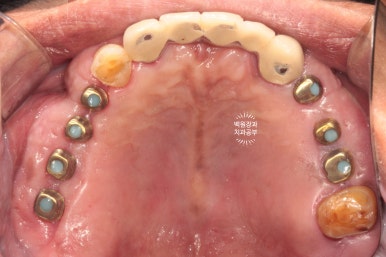

위 아래 교합면 사진입니다.

임플란트를 교합면에서 보았을 때, 잘 식립되어 있는 경우 저렇게 동그라미들을 보실 수 있습니다.

바로 screw hole 인데요, 추후 임플란트를 수리해야 할 일이 있을 때, 다시 개방하는 screw 입구입니다.

현재는 레진으로 메꿔져 있어요.

아래 어금니 지르코니아 크라운들도 해부학적 형태가 잘 재현되어 있고,

조화로운 모양과 색상으로 거의 자연치와 흡사한 형태를 보여주고 있어요.!!!

위의 두 장의 사진이 저희 병원에 처음 내원하셨을 때의 사진입니다.

아래 두 장의 사진은 저희 병원에서 약 9개월간의 치료를 받으신 후의 결과이구요.

식사가 거의 불가했던 환자분이 어금니를 회복함으로 인해 양쪽으로 식사가 가능한 상태가 되셨고,

뿌리만 남아 기능적, 심미적으로 불량했던 아래 앞니는 임플란트 치료를 통해 올바른 길이와 모양으로 재탄생 하였습니다.